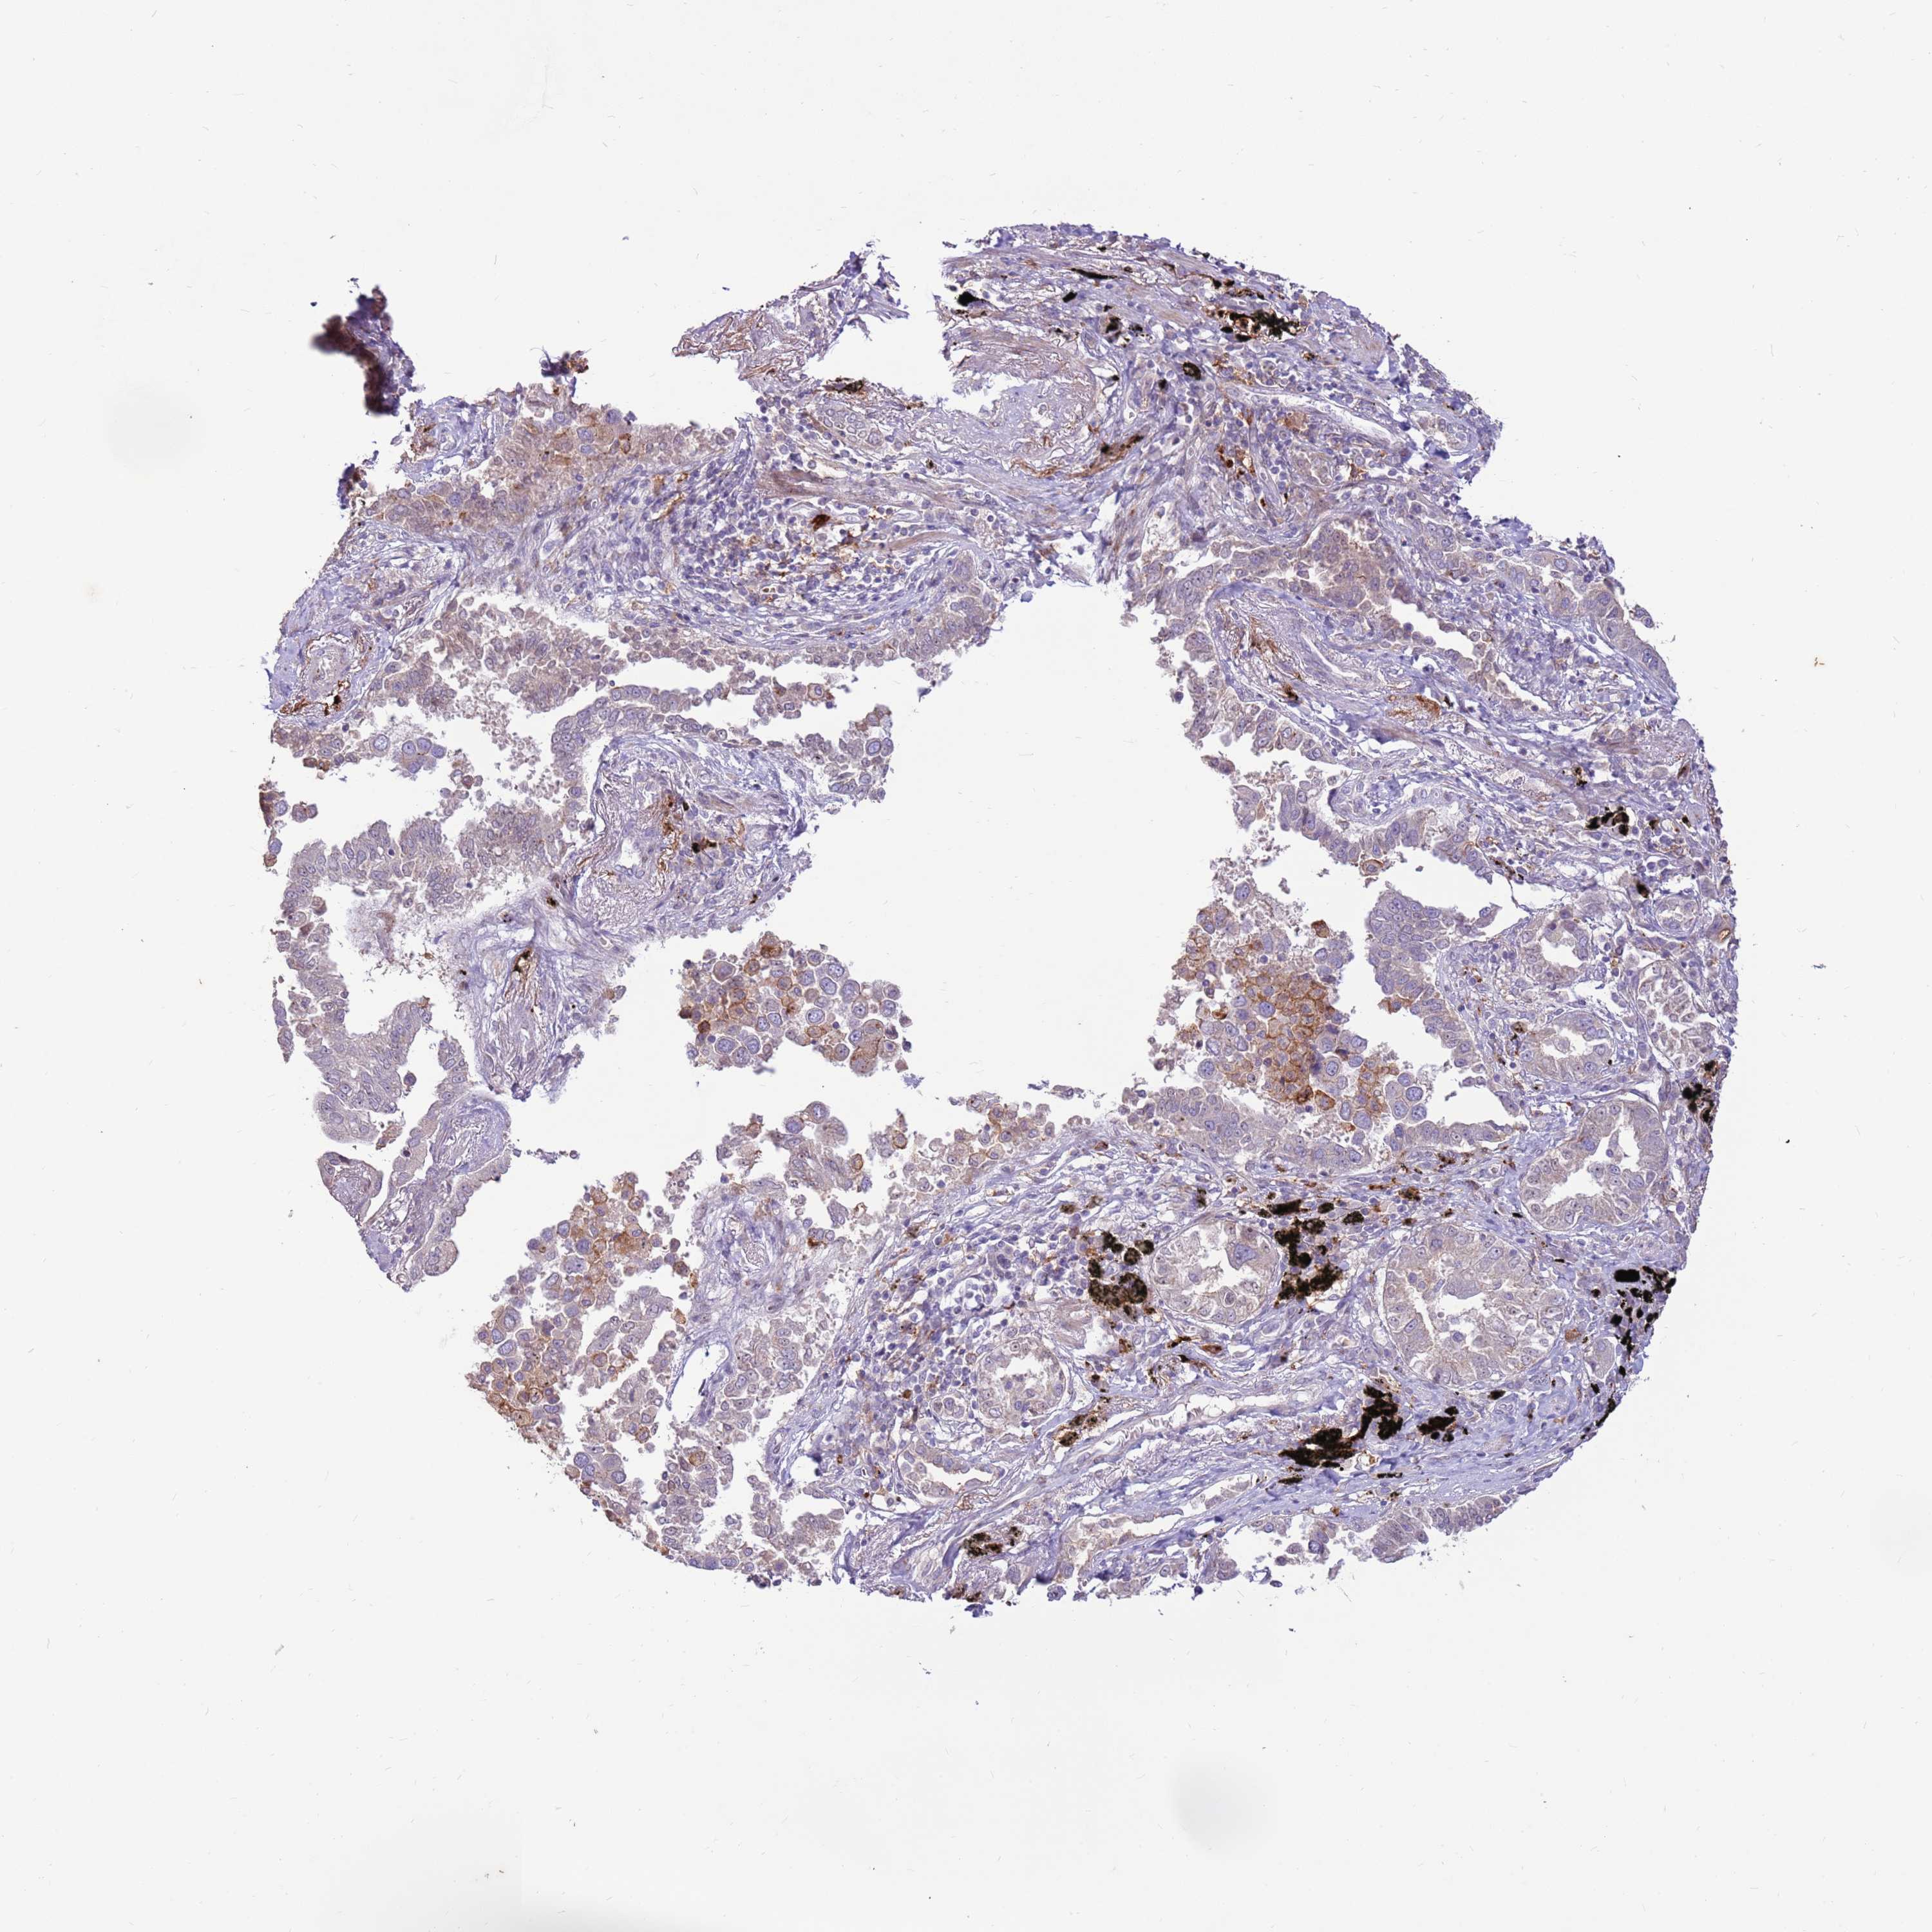

LUNG ADENOCARCINOMA (VALIDATION) - Interactive survival scatter ploti

The Survival Scatter plot shows the clinical status (i.e. dead or alive) for all individuals in the patient cohort, based on the same data that underlies the corresponding Kaplan-Meier plots. Patients that are alive at last time for follow-up are shown in blue and patients who have died during the study are shown in red.

The x-axis shows the expression levels (FPKM) of the investigated gene in the tumor tissue at the time of diagnosis. The y-axis shows the follow-up time after diagnosis (years). Both axes are complimented with kernel density curves demonstrating the data density over the axes. The top density plot shows the expression levels (FPKM) distribution among dead (red) and alive patients (blue). The right density plot shows the data density of the survived years of dead patients with high and low expression levels respectively, stratified using the cutoff indicated by the vertical dashed line through the Survival Scatter plot. This cutoff is automatically defined based on the FPKM cutoff that minimizes the p-score. The cutoff can be changed by dragging the vertical line or by entering a cutoff value in the square labeled "Current cut-off".

Under the Survival Scatter plot the p-score landscape (black curve; left axis) is shown together with dead median separation (red curve; right axis). Dead median separation is the difference in median mRNA expression between patients who have died with high and low expression, respectively. It is calculated as follows: median FPKM expression of dead patients with high expression - median FPKM expression of dead patients with low expression. This is intended to aid the user in visually exploring custom cutoffs and the associated p-scores and dead median separation.

Individual patient data is displayed and can be filtered by clicking on one or more of the category buttons on the top of the page. Categories describing expression level and patient information include: high, low, alive, dead, female, male and tumor stages. The scale of the x-axis can be toggled between linear and log-scale by clicking on the "x log" button. Mouse-over function shows TCGA ID, patient information and mRNA expression (FPKM) for each patient.

& Survival analysisi

Kaplan-Meier plots summarize results from analysis of correlation between mRNA expression level and patient survival. Patients were divided based on level of expression into one of the two groups "low" (under cut off) or "high" (over cut off). X-axis shows time for survival (years) and y-axis shows the probability of survival, where 1.0 corresponds to 100 percent.

LGI4 is not prognostic in Lung Adenocarcinoma (validation)